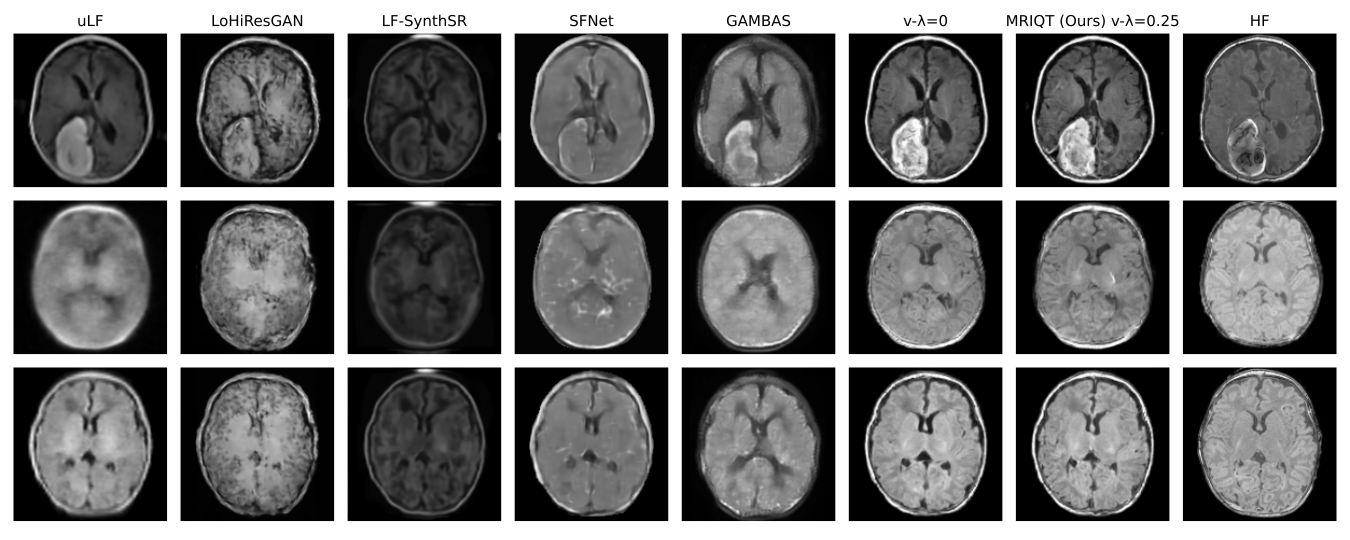

Quntitative and Qulaititative Results

A comparison of our MRIQT with other competitirs w.r.t PSNR, LPIPS, MAE, MS-SSIM, SSIM, and Pearson Correlation metrics: